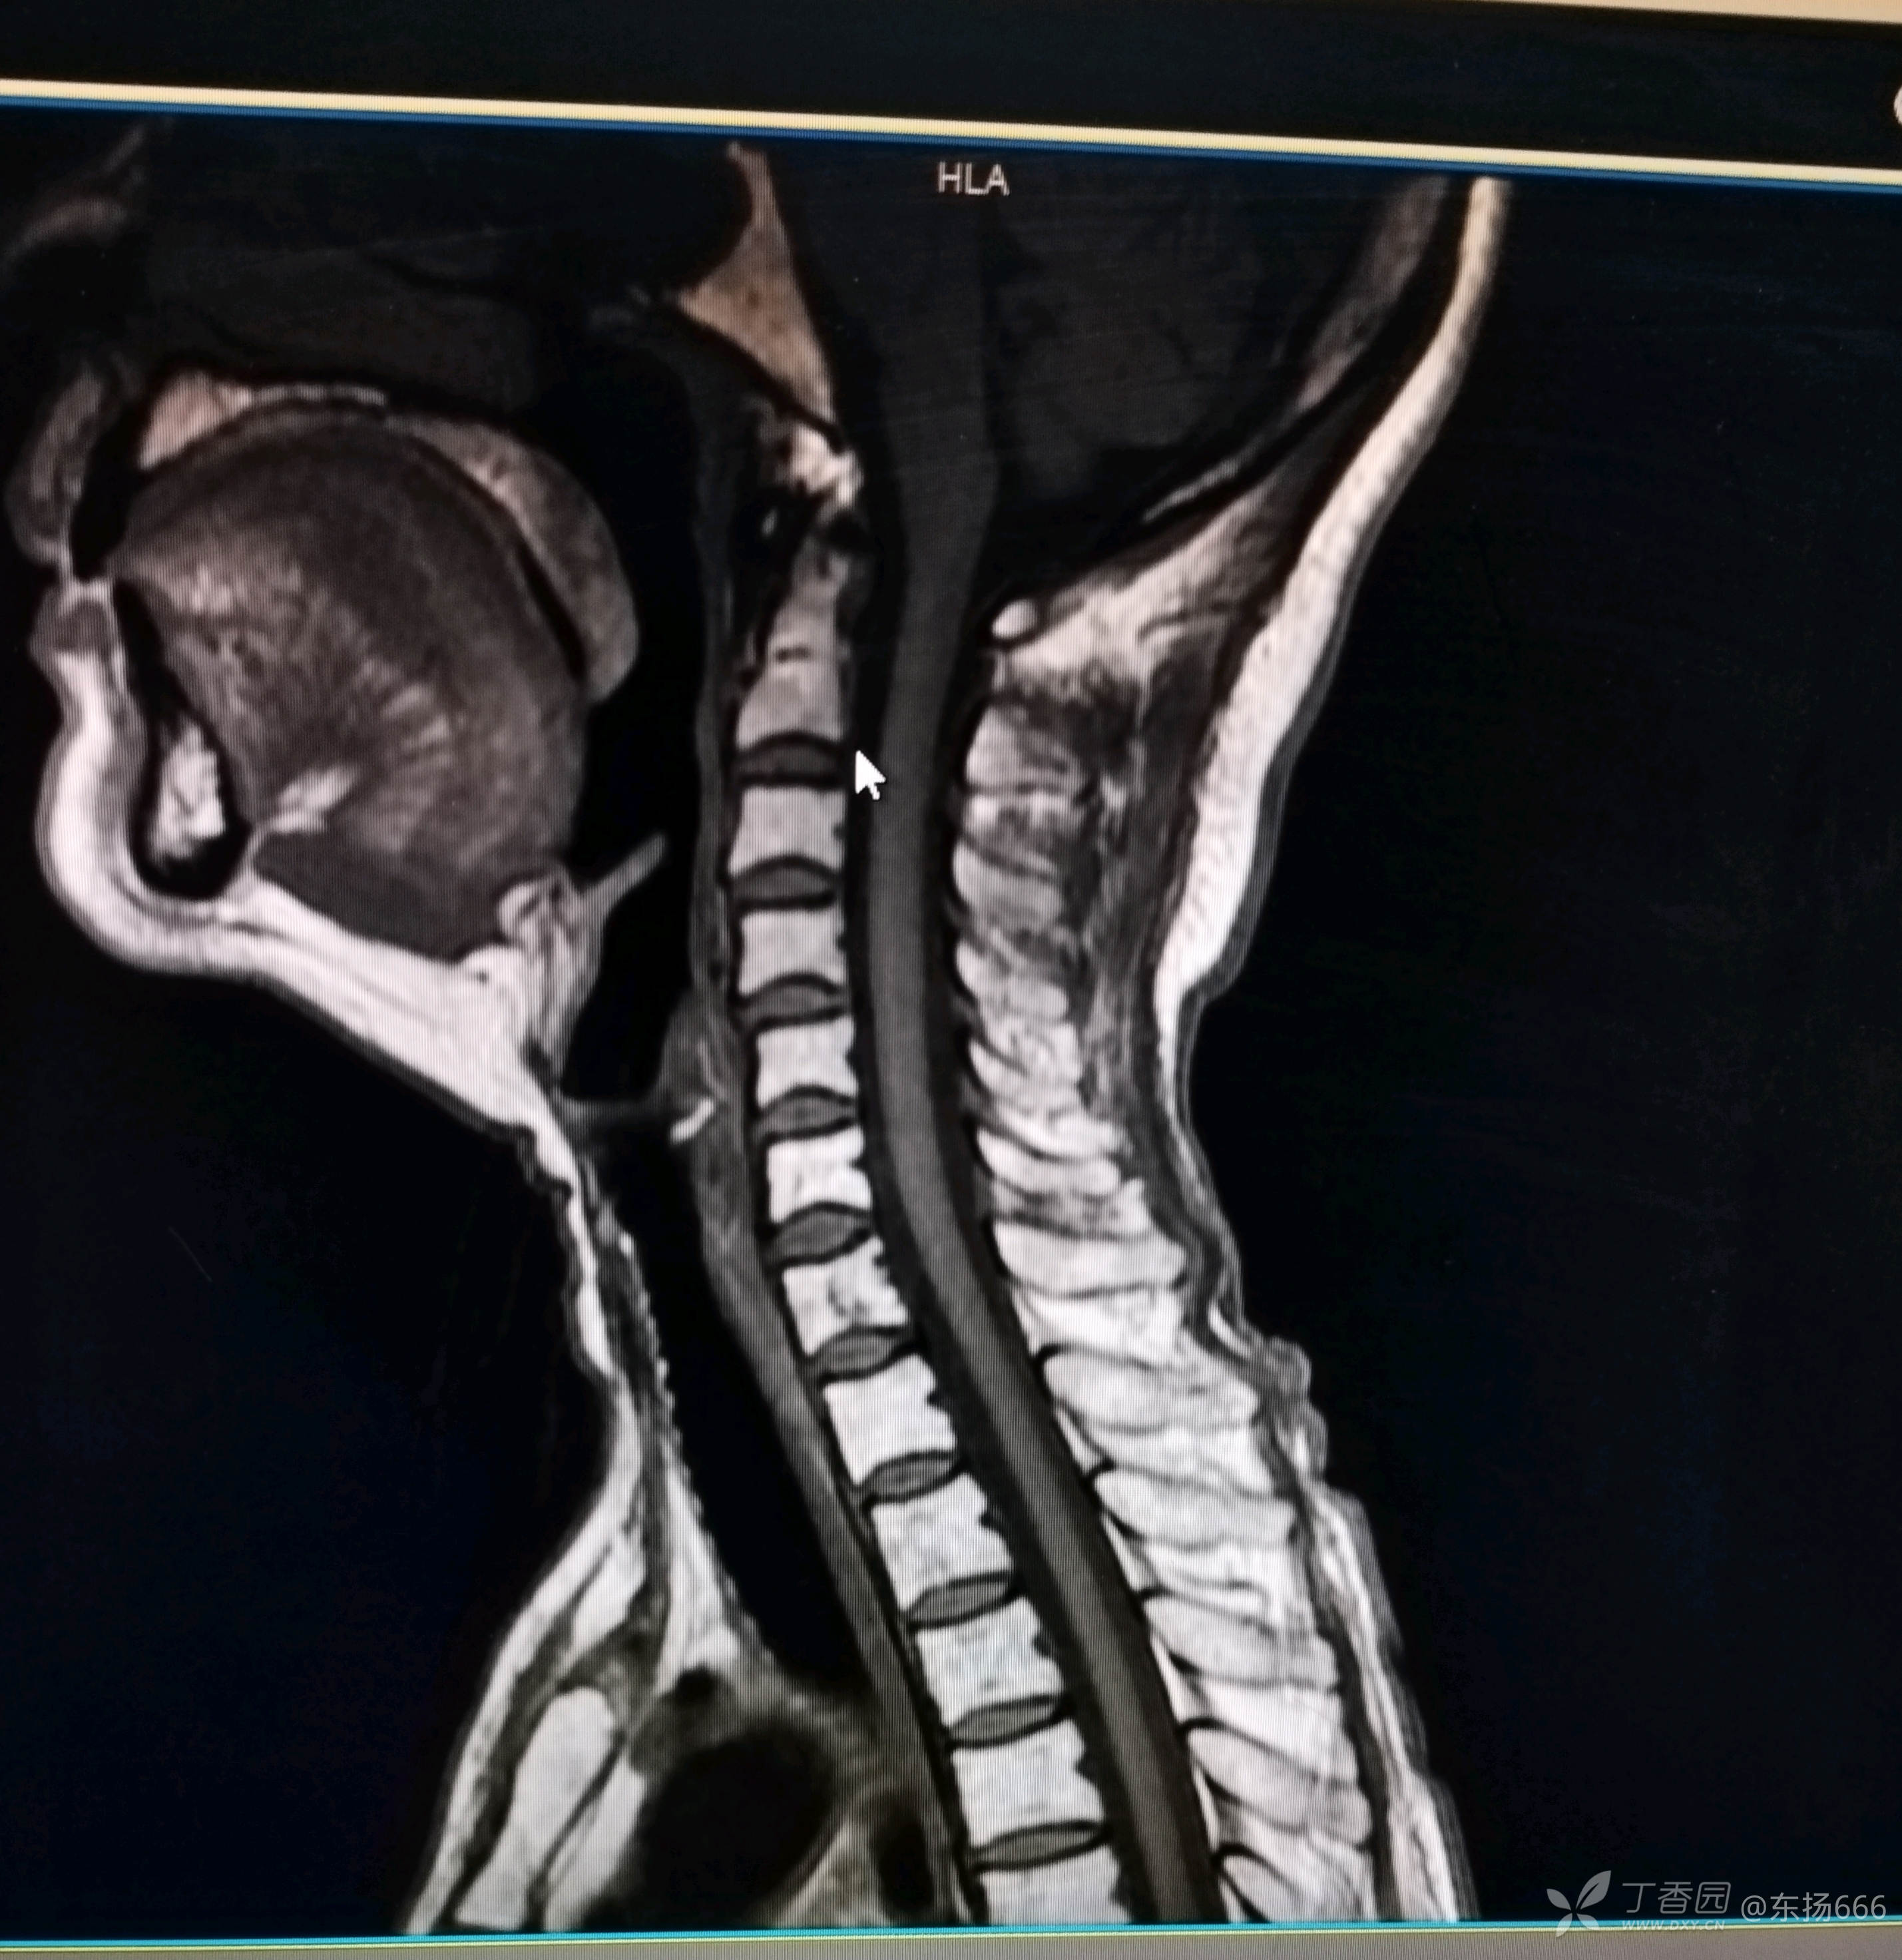

我院行颈椎MR示:颈椎间盘退行性病变。C2-7椎间盘突出